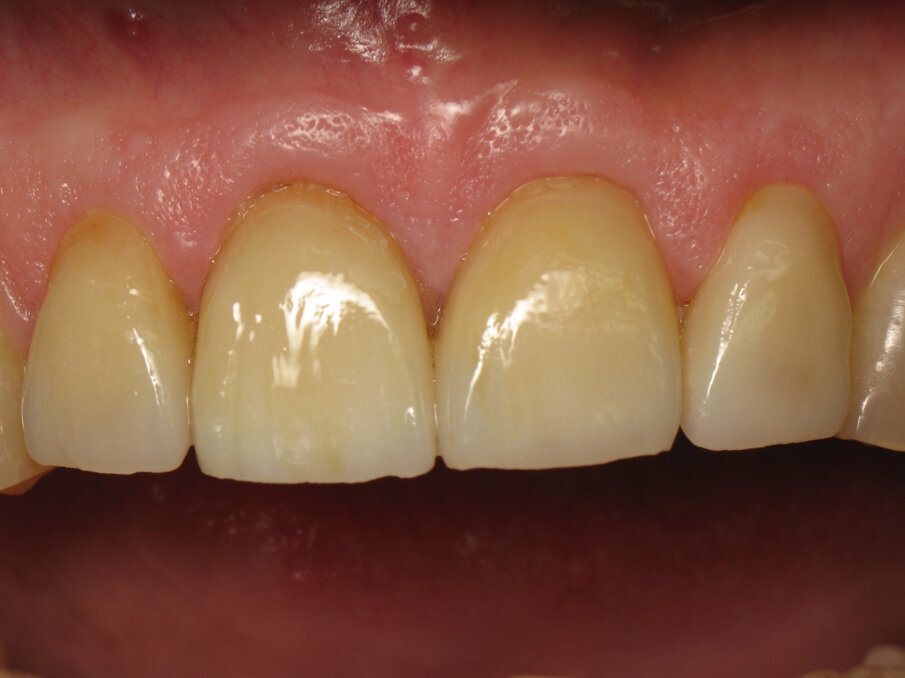

Figure 1 shows a clinical situation in which the patient will be able to smile literally and figuratively. The teeth have a harmonious shape, position and shade, despite minor defects such as cervical lesions of the mandibular incisors. There is also good periodontal health, there being no plaque or gingivitis. What the reader is far from suspecting is that this final situation corresponds to the placement of four crowns on teeth #12–22.

Figure 2 shows us close up the quality of the restorations and the care taken by the dental technician in the production of these crowns. Indeed, the anatomy is harmonious and leaves no black triangles at the gingival papillae. In addition, the shade is natural, saturation increasing gradually from the incisal edge to the cervical region. The laboratory technician added a subtle touch of ochre stain in vertical lines. Particular attention has been paid to this clinical case for a result that exceeded the patient’s expectations.